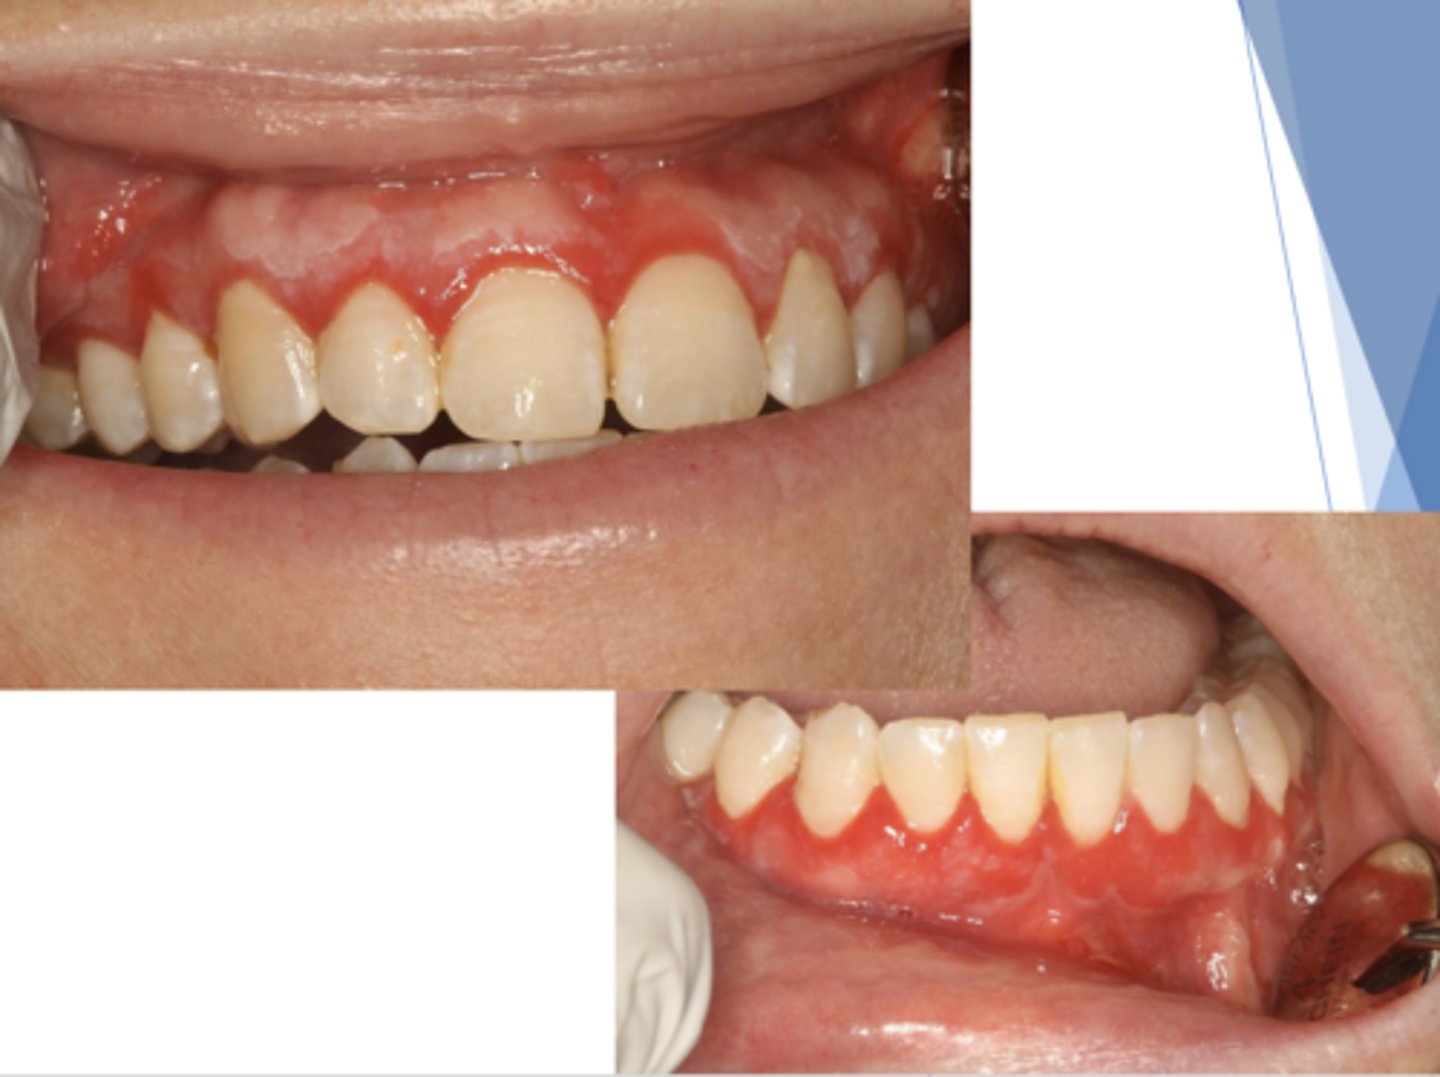

lichen planus (erosive/erythematous)

What type of lichen planus?

- Often symptomatic

- Striae at periphery of erythema

- May cause desquamative gingivitis

- Must be distinguished from mucous membrane pemphigoid or pemphigus

What condition?